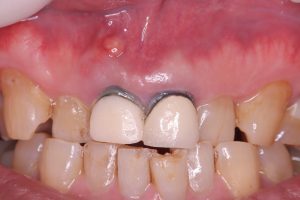

午前にインプラントオペ、ソケットシールド併用

抜歯即時、即時荷重仮歯まで予定

審美エリアだから、歯が無いと困る😅

フラップレス切開無しno incision